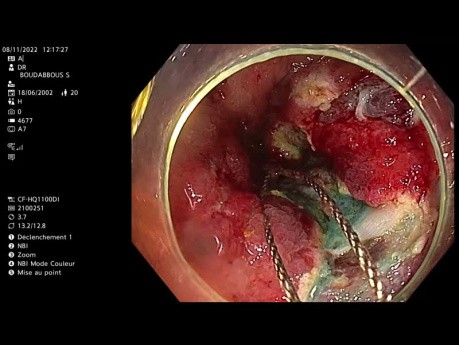

Résection Muqueuse Endoscopique du Côlon Ascendant...

Cas vidéo endoscopique : homme de 20 ans avec antécédents de maladie de Crohn, résection iléo-caecale il y a 8 ans, découverte au dépistage par colocopie d'un gros LST (Tumeur à extension larérale) dans...